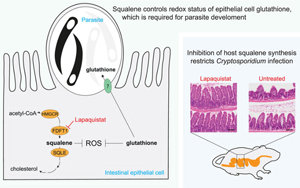

揭示宿主膽固醇代謝通路中角鯊烯調控隱孢子蟲生存的關鍵機制及其治療潛力

英國弗朗西斯·克里克研究所(The Francis Crick Institute)的研究團隊另辟蹊徑,通過創新的顯微成像CRISPR篩選技術,發現宿主細胞的膽固醇合成通路竟成為隱孢子蟲的"阿喀琉斯之踵"。研究人員構建了包含18,466個人類基因的陣列式CRISPR-Cas9敲除庫,結合高內涵成像定量分析感染參數,首次系統繪制了宿主基因調控寄生蟲生長的多維圖譜。